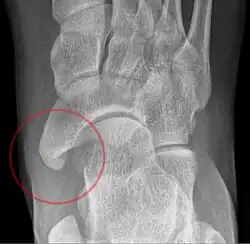

Beim Os tibiale externum (synonym: Os naviculare externum, Os naviculare secundarium, Os naviculare accessorium, Os naviculare bipartitum; englisch accessory tarsal navicular, accessory tarsal scaphoid) handelt es sich um eine häufige (10–16 %) Variation am Kahnbein des Fußes (Os naviculare). In über der Hälfte der Fälle tritt es beidseitig auf.

Es ist eine harte Auftreibung im Sinne eines Überbeins an der inneren Fußwurzel, etwa einen Fingerbreit unter und vor der Innenknöchelspitze, also am Kahnbein, tastbar. Gelegentlich tritt ein Belastungs- und Druckschmerz auf, insbesondere, wenn diese Fehlbildung zusammen mit einem Plattfuß auftritt. Die Diagnose wird mit einem Röntgenbild gesichert.

Es sind drei Formen des Os tibiale externum zu differenzieren:

- Typ 1: Das Os tibiale externum im engeren Sinne ist ein 2–3 mm großes, rundliches Sesambein im Ansatzbereich der Sehne des Musculus tibialis posterior. Es bildet keinen Knorpel zum Kahnbein.

- Typ 2: Das Os tibiale externum ist dreieckförmig und bis zu 9 mm groß. Dieses hat eine Knorpelverbindung zum Kahnbein. Dieser Typ ist mit über 50 % der häufigste. Es handelt sich um eine unterbliebene Verschmelzung der Knochenkerne, aus denen sich das Kahnbein in der frühen Jugend bildet.

- Typ 3: Hier ist das Kahnbein anlagemäßig weit ausladend nach innen ausgebildet (Os naviculare cornutum, englisch cornuate navicular). Hier ist im Gegensatz zu den ersten beiden Formen kein Spalt auszumachen.